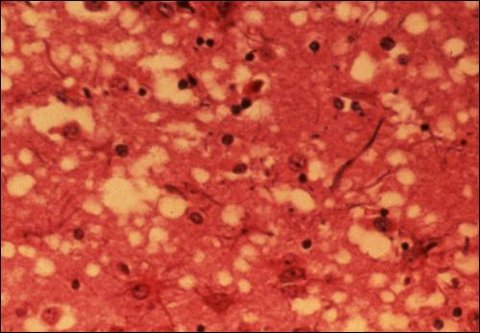

옆의 사진을 보시면 광우병에 걸린 소의 뇌사진입니다. 이렇게 광우병에 걸린 소를 인간이 먹으면 우리도 광우병에 걸리게 됩니다. 인간도 광우병에 걸리면 뇌에 저렇게 구멍이 나는거죠. 저렇게 뇌에 구멍이 생기면 어떻게 될까요 ? 공격적 성향, 무감동증 등의 정신적인 증상이 먼저 나타난다고 합니다. 이어서 기억장애 감각장애, 무언증 인지장애 등이 나타난다고 합니다. 이것은 치매와 비슷하죠. 그리고 이 광우병은 치료방법도 없습니다. 치료방법은 커녕 광우병의 원인인 프라이온이란 것은 600도의 고온에서도 죽지 않는 다고 하죠.